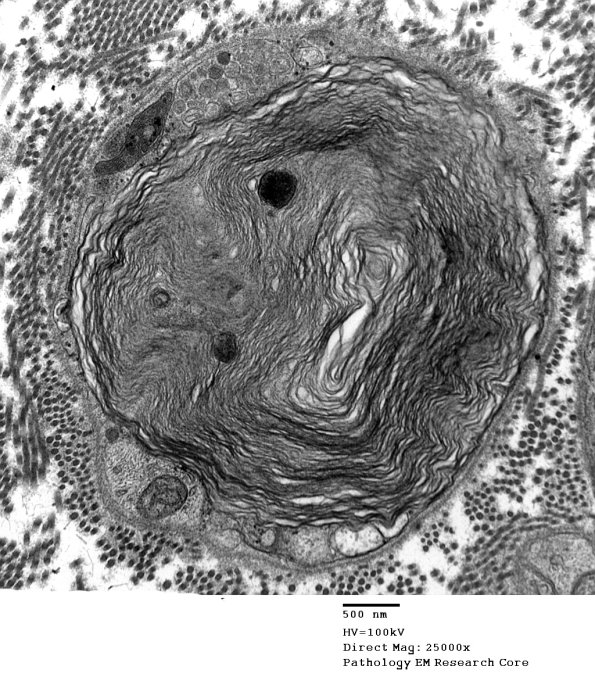

Washington University Experience | PERIPHERAL NEUROPATHY | 4 AXONAL DEGENERATION | 3 Electron Microscopy | 6D Axonal Degeneration (Case 7) EM 027 - Copy

In chronic neuropathies it is not uncommon to see lipidic debris remaining within Schwann cell processes as myelin residua in an inactive nerve.